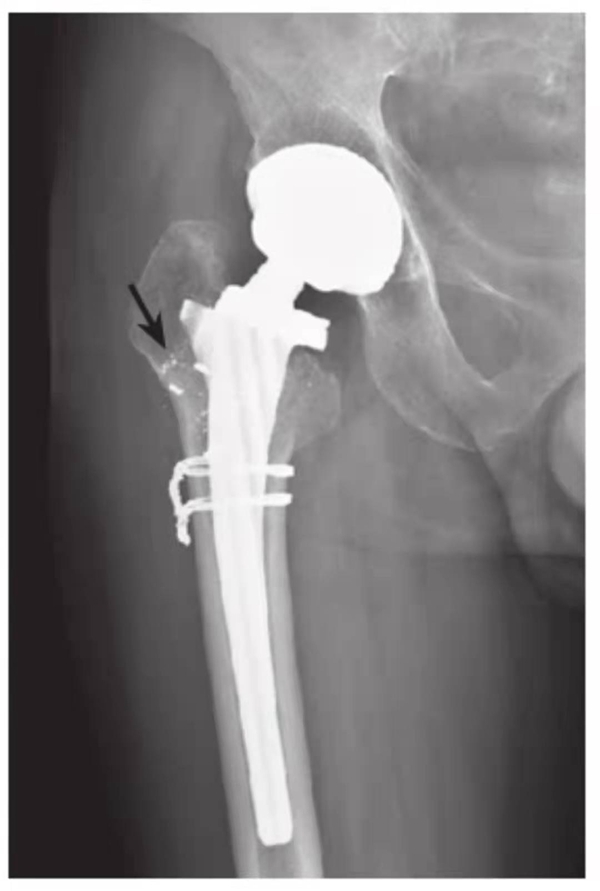

图4 右侧人工髋关节置换术后感染并松动

女性,89岁。发现右大腿中段后侧流脓2个月余。平片,示右股骨上段骨密度增高,内侧骨膜增生,假体周围骨质吸收,髋臼杯内陷,人工股骨柄部内移